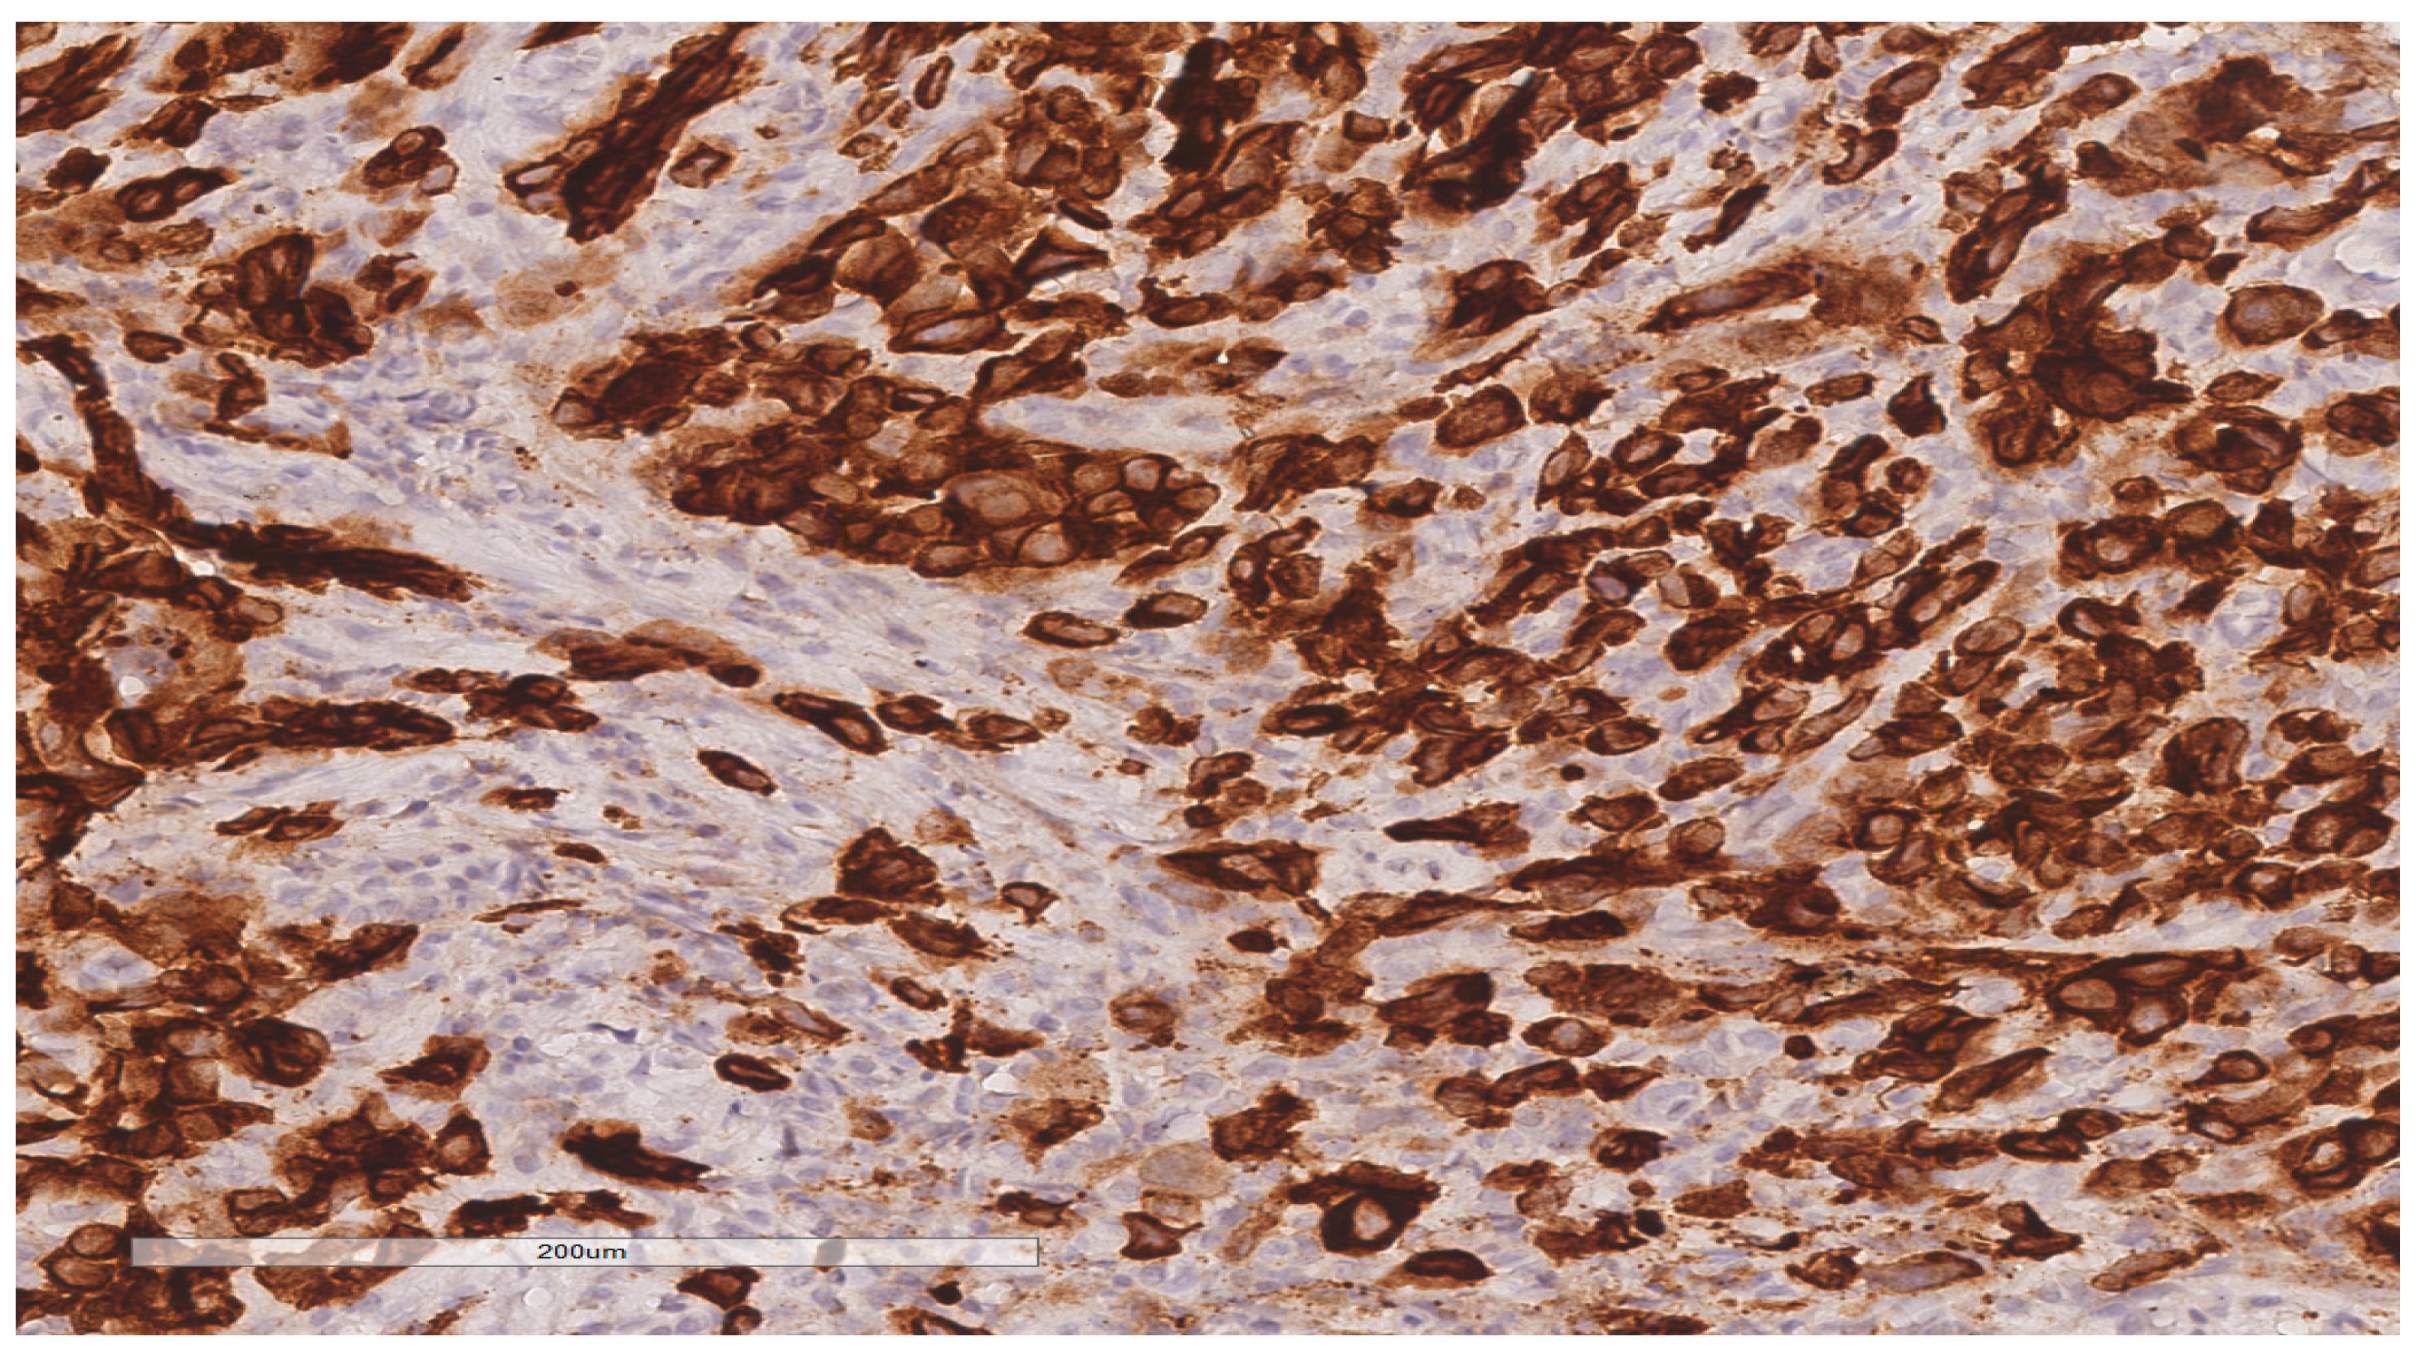

2.3. Surgical Procedure and Pathological Findings